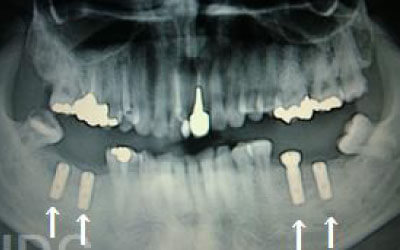

2 神経を傷つけるリスク

顎の骨の中を通っている神経を傷つけるリスクがあります。

ただ、事前にしっかりCT撮影して三次元的に神経までの距離を計測して治療計画を立てれば心配することはありません。

また削りすぎないためのストッパーも当院では使用しております。